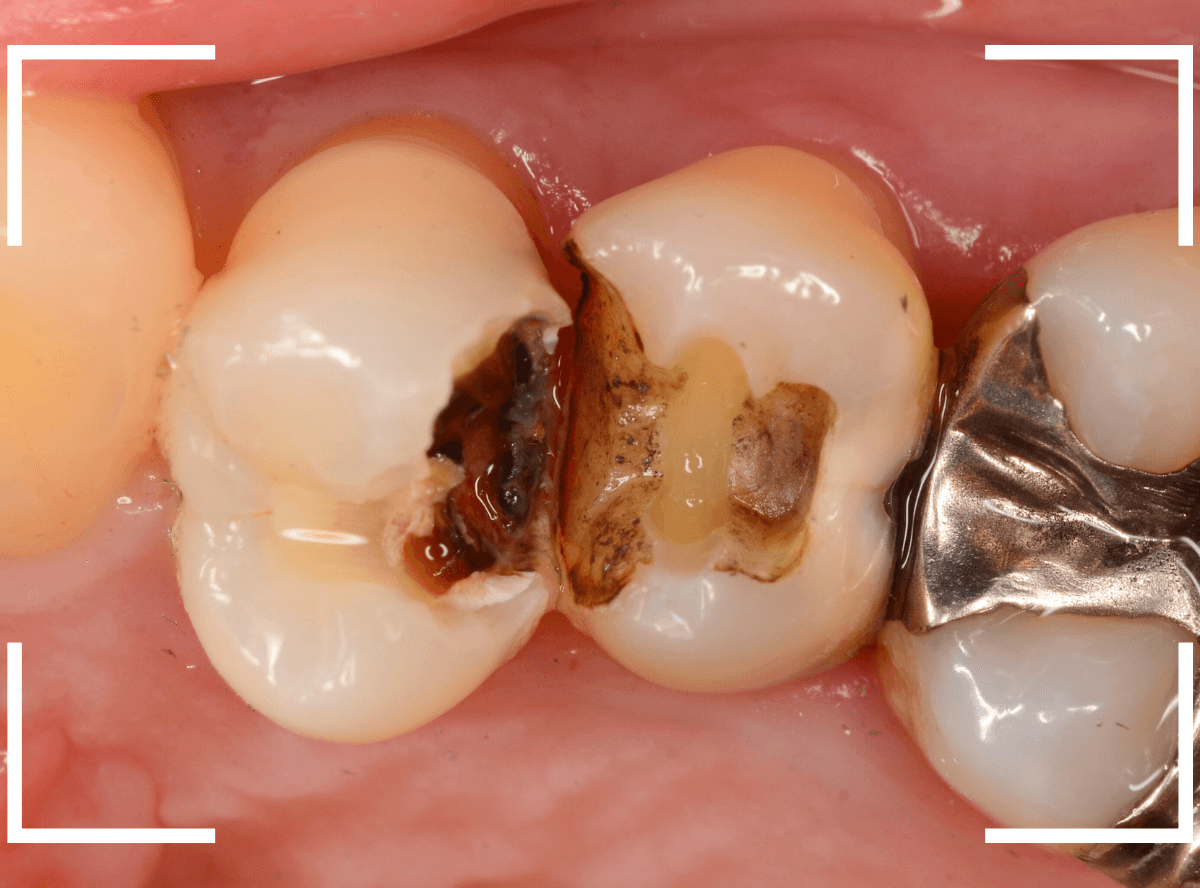

Case.23 歯のすきまから両側が大きな虫歯

「下の奥歯が痛む」という訴えで来院された患者さんのケースです。

目視でも、手前の奥歯がかけていて、中で虫歯が広がってるであろうことは予想できます。

ピンセットで歯を叩いてみても、手前の奥歯が痛むようです。

レントゲン写真で確認します。

青い線が神経、赤い線が虫歯の範囲です。

奥歯の方がより深い虫歯に見えますが、再度打診で確認したところ、やはり手前の奥歯が痛むそうです。

状況から、まず手前の奥歯から治療となりました。

麻酔をして、手前の奥歯のレジンを慎重に外します。

前に虫歯の治療をした時点で、神経スレスレの状態でしたので、削りすぎないように慎重にレジンを外さなければいけません。

レジンを外して、う蝕検知液で確認します。

レジンの中で虫歯が進行していたのがわかります。

慎重に全ての虫歯を除去しました。

何とか、神経が露出せずに済んでいます。

お薬をつめて、セメントで蓋をして経過観察します。

後日、状況を確認したところ、虫歯処置した後も、手前の奥歯が痛むとの事でした。

「我慢できないほどでもない」との事でしたので、引き続き経過観察しつつ、奥歯の治療を治療する事になりました。

奥歯は、レントゲンで見た通り、少し歯を削るとすぐに虫歯の穴が出てきました。

こちらは、ある程度虫歯を取ったところで染め出してみると真っ赤です。

ですが、何とか神経に達する前に、全ての虫歯を除去できました。

神経の治療が必要かと思っていたので、その点は幸運でした。

奥歯もお薬をつめて、セメントで蓋をして経過観察です。

何とか神経を取らずに済ませたいですが、どうなる事か・・・。